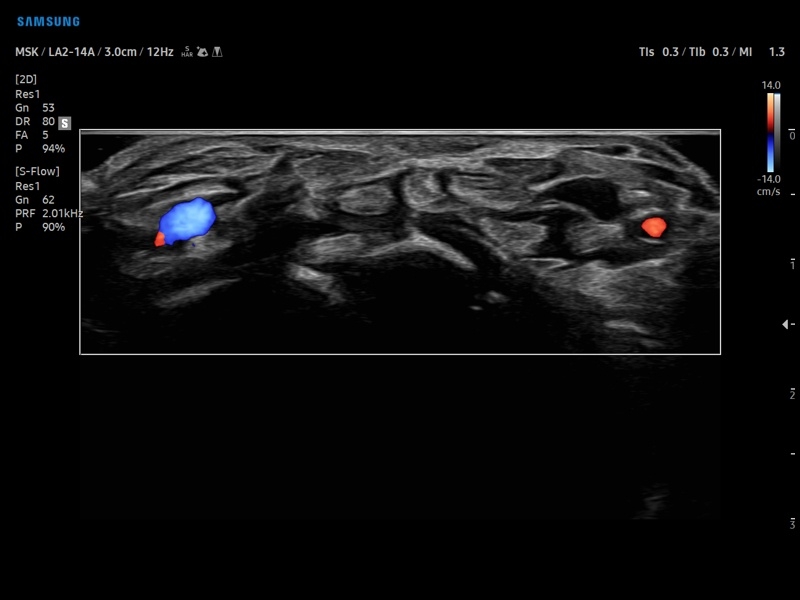

• Программа SEE Stream – режим недопплеровской визуализации кровотока в реальном масштабе времени.

• Модуль MV-Flow - программа (режим), позволяющая визуализировать кровоток в микроциркуляторном русле с высоким разрешением без использования контраста.